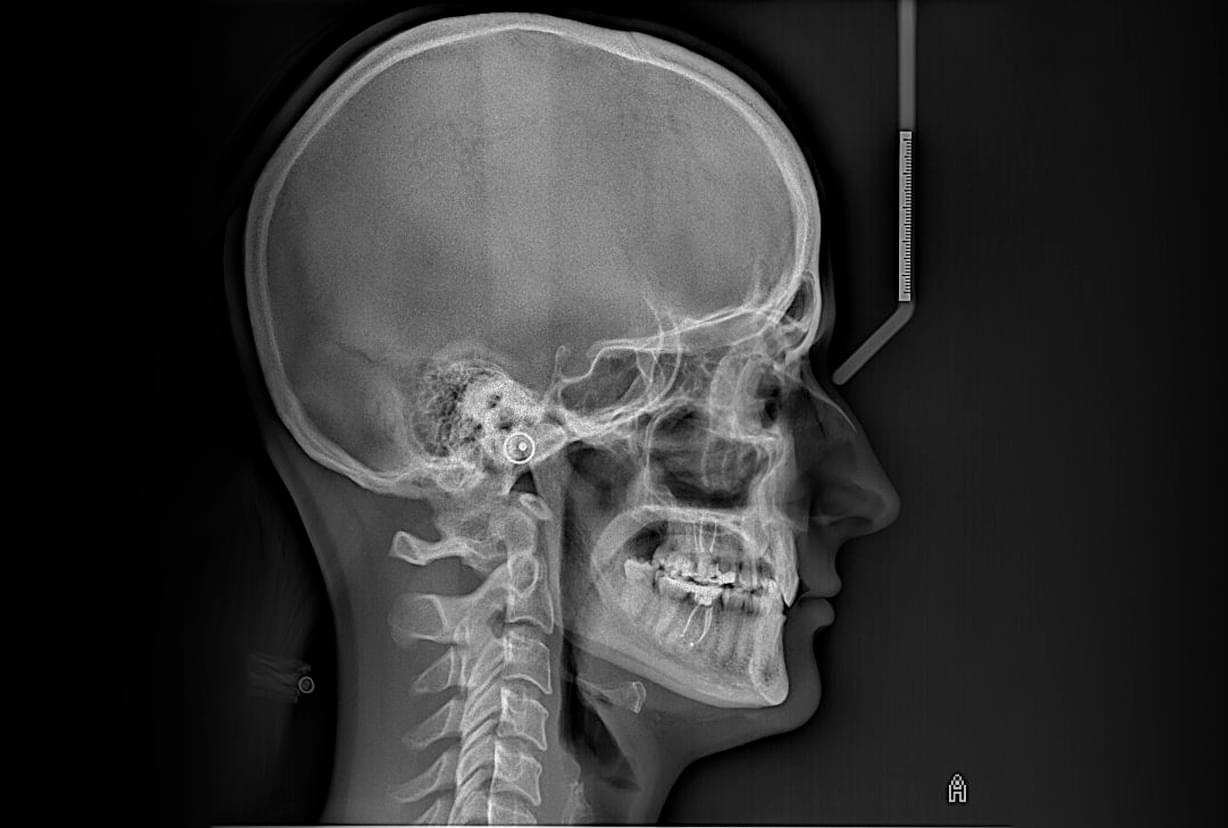

1️⃣ ТРГ у боковій проекції (Профіль)

● Це «золотий стандарт» перед початком ортодонтичного лікування.

● Що показує: Вигляд черепа збоку. Дозволяє оцінити профіль обличчя, нахил різців, як верхня

щелепа співвідноситься з нижньою.

● Для чого: Щоб спланувати виправлення прикусу (наприклад, якщо нижня щелепа висунута вперед або

занадто засунута назад).